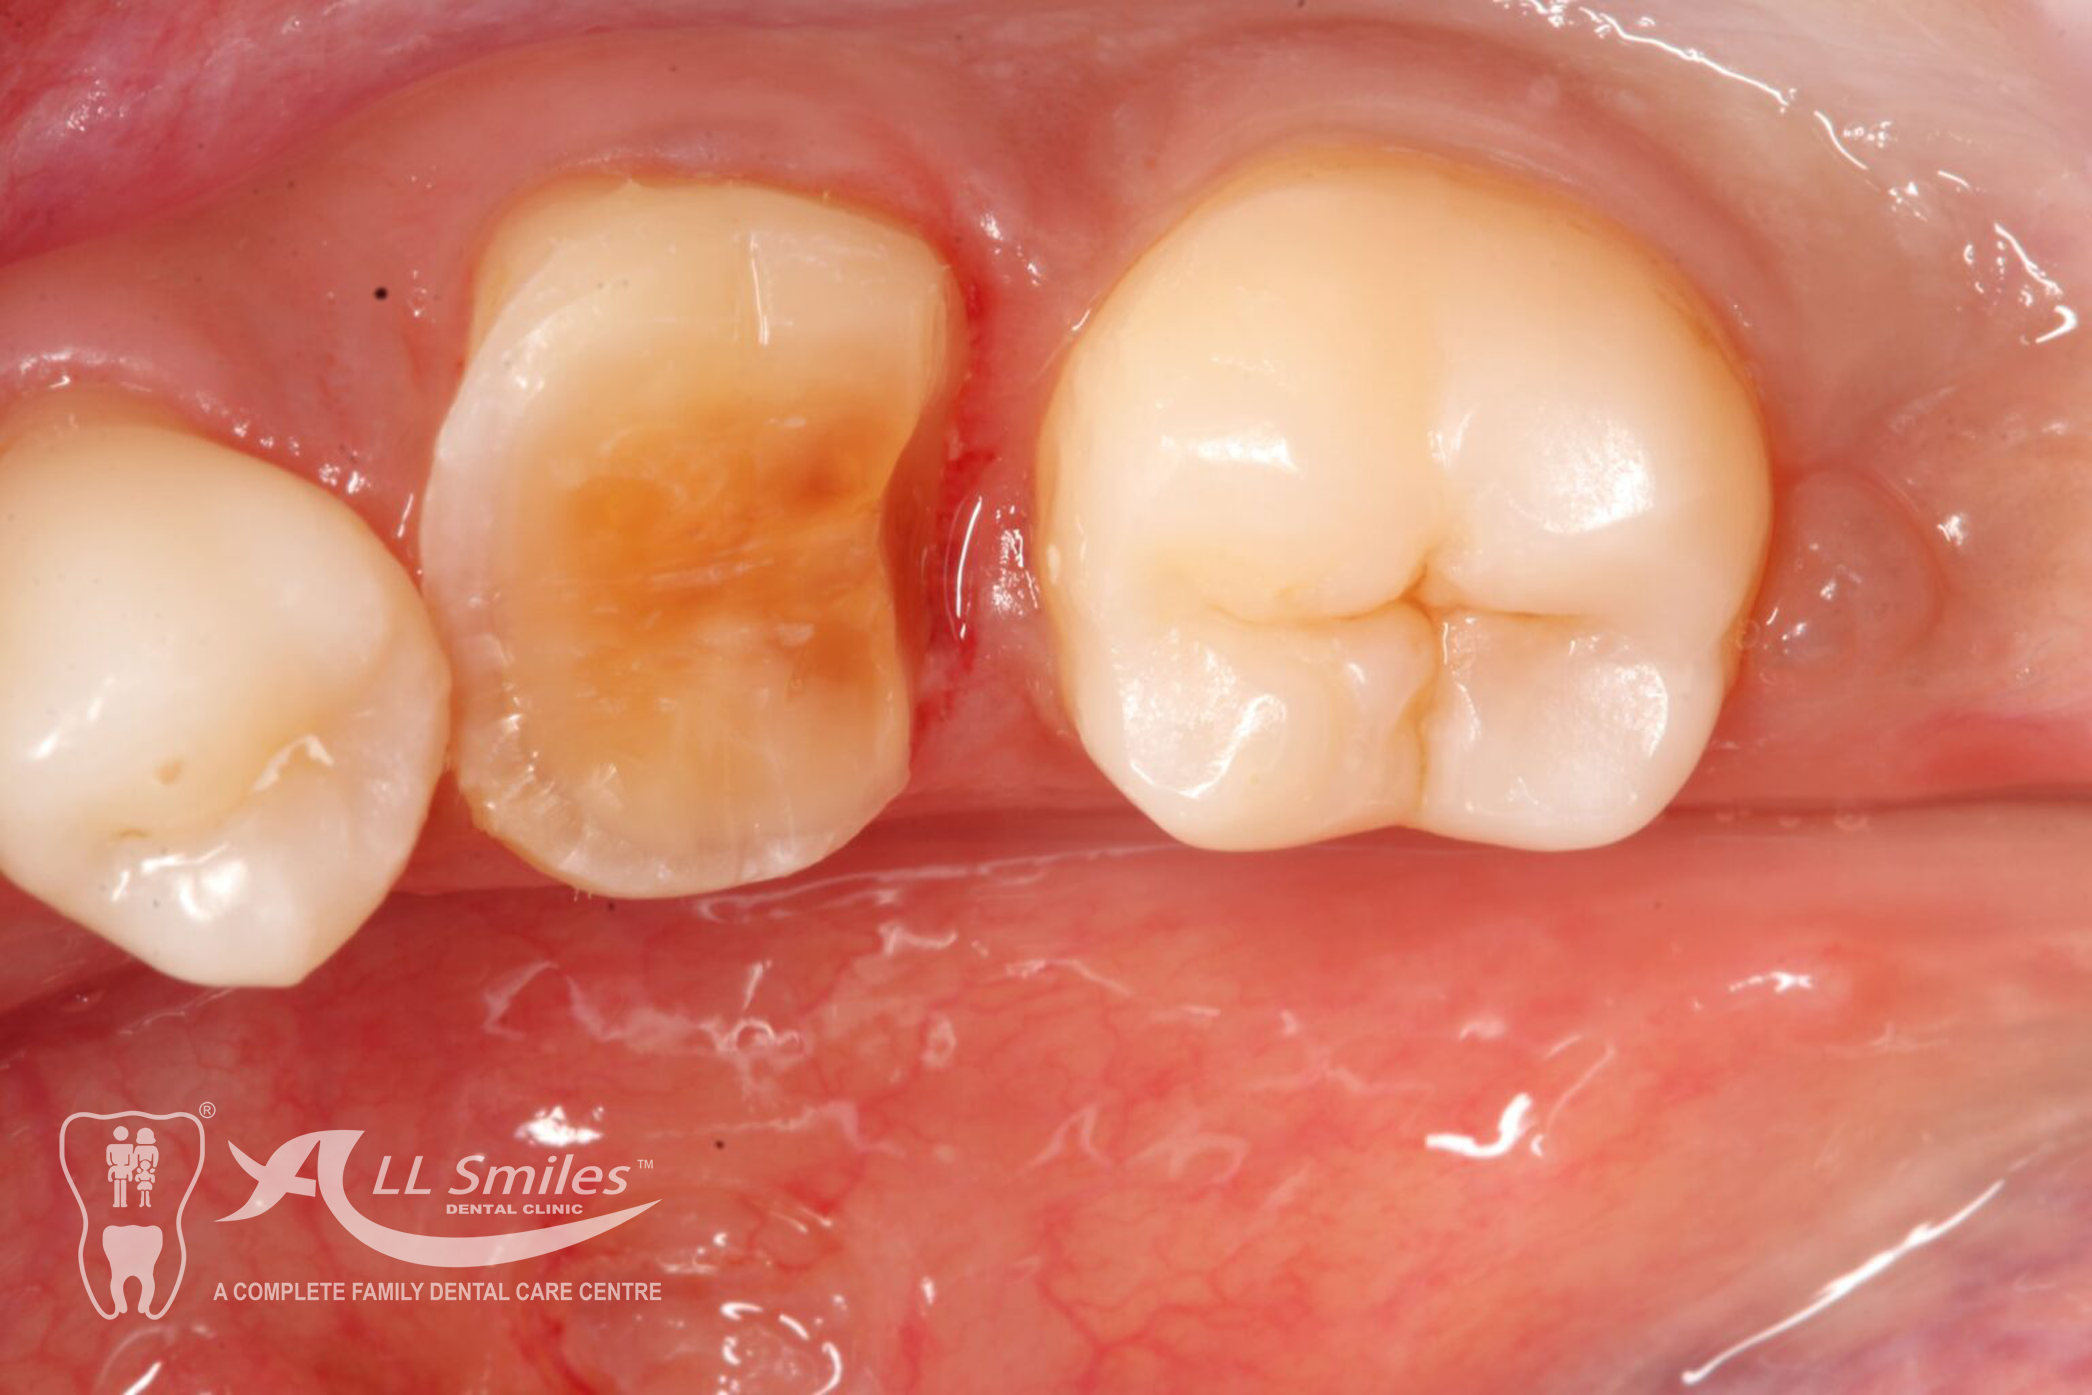

Crowns & Bridges Gallery